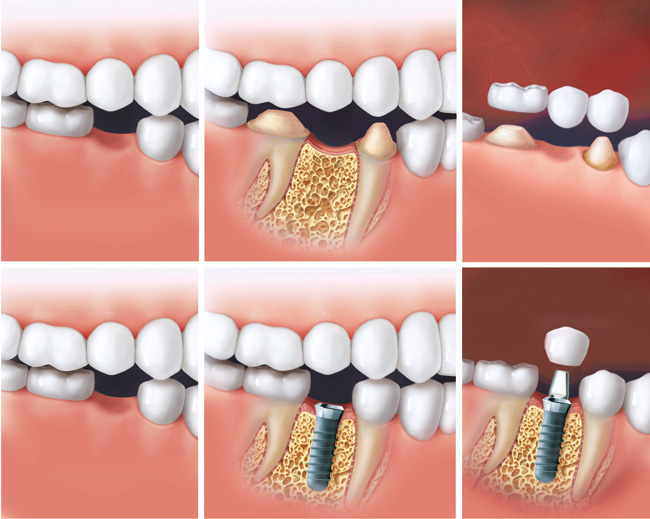

پروتز ثابت بر روی دندان یا دندان های پایه چسبانده می شود و یا در ناحیه بی دندانی، کاشت می شود. پروتز ثابت از نظر اندازه، شکل و زیبایی به دندان اصلی نزدیکتر بوده و شامل موارد زیر است :

الف- بریج و روکش

جهت بازسازی و اضافه کردن دندان های از دست رفته و یا دندان های ترمیم شده با دیواره های ضعیف، پایه ها از همه ابعاد تراش خورده، از آن قالب گیری شده و توسط تکنیسین لابراتوار بصورت های سرامیک، چینی و پرسلن و فلز و گاه با آلیاژ طلا ساخته می شود. مقاومت آن در مقابل سایش و نیروی جویدن بالا بوده، رنگ، شفافیت و زیبایی آن به دندانهای دیگر نزدیک تر و قابل قبول تر است. اگر پروتز ثابت ساخته شده تک واحدی باشد، روکش و در صورت جایگزینی چندین دندان از دست رفته،بریج نامیده می شود که در بیش از یک جلسه آماده می گردد. طول عمر روکشها بین ۵ تا ۱۵ سال است که دوام آن به مهارت تکنیسین لابراتوار، تراش صحیح دندانپزشک و رعایت بهداشت توسط بیمار بستگی دارد.

ب- ایمپلنت یا کاشت دندان

ایمپلنت علم جدیدی است که برای باز گرداندن دندانهای از دست رفته با ساخت پایه هایی برای گیر و نصب پروتز متحرک،پیچهایی ازجنس فلزتیتانیوم در داخل استخوان فک با عمل جراحی گذاشته می شود که استحکام یک دندان طبیعی را خواهد داشت. پس از قالب گیری، ساخت پروتز در لابراتوار انجام می گیرد.